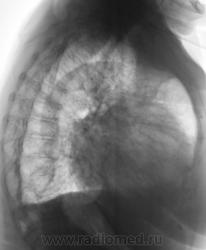

При расшифровке цифровых флюорограмм пациент "взят на контроль". Произведено стандартное исследование.

На рентгенограммах (в отличии от томо) на верхушке ничего не заметил. А так, похоже на митр. недостаточность.